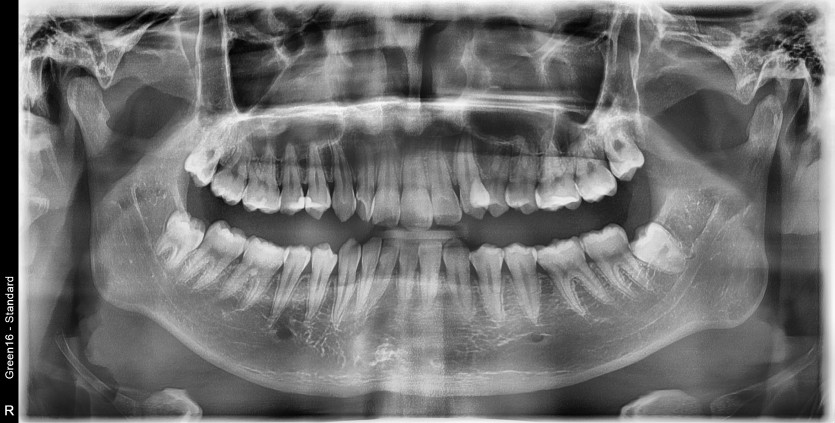

#18, 48 사랑니 발치

구강 외과 전문의가 당일 발치했습니다.